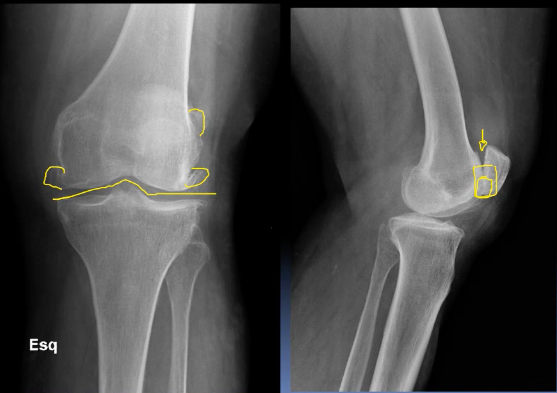

A 30 year old man presented to the ED with left knee pain after a cycling accident.

On examination there was no deformity, but it was painful for him to weight-bear. Movements of his knee were painful, and this limited his movements.

What is a lipohemarthrosis?

Results from an intra-articular fracture with escape of fat and blood from the bone marrow into the joint, and is most frequently seen in the knee.

What normal variant can be seen in this image?